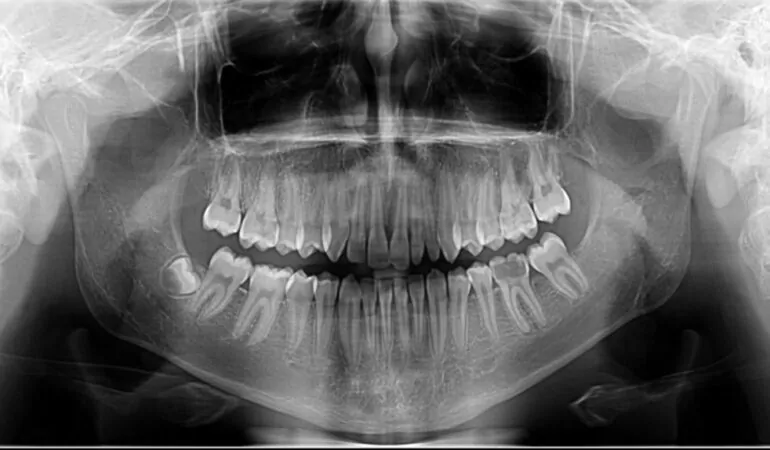

Radiografia dentară este o imagine a dinților, osului și țesuturilor moi din jur, care ajută la depistarea afecțiunilor dentare. Acestea pot scoate la iveală cariile dentare, structuri ascunse, cum sunt dintii inclusi (neerupti), precum și pierderea osoasă, afecțiuni care nu se pot observa cu ochiul liber. Radiografiile pot fi utilizate și după realizarea unui tratament pentru a verifica succesul acestuia.